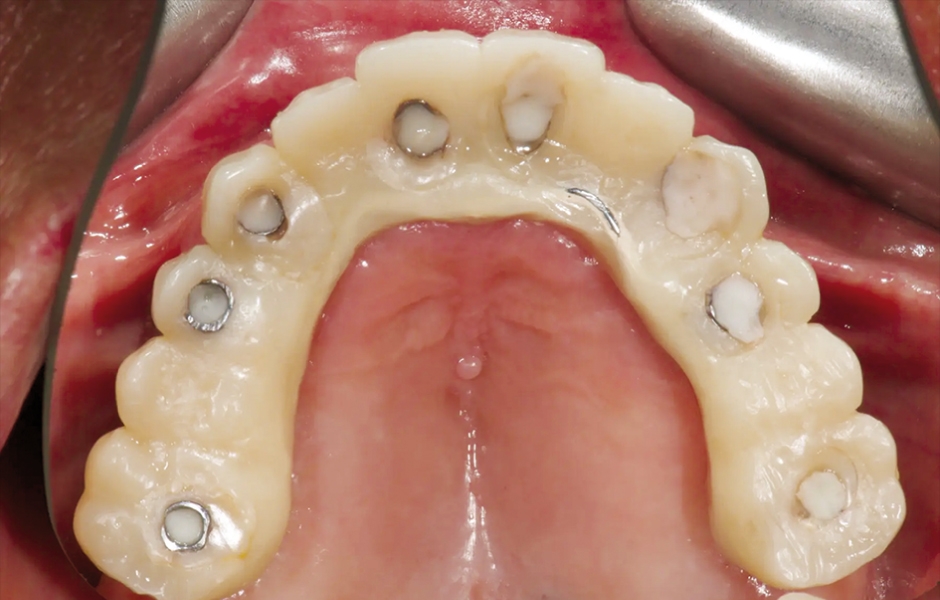

V den operace byla aplikována lokální anestezie a první chirurgická šablona byla stabilizována na zbývajících zubech k přípravě pěti fixačních pinů. Poškozené zuby byly extrahovány a druhá chirurgická šablona byla upevněna v připravených místech. Osm implantátů (Osstem TSIII SOI, Osstem Implant) bylo umístěno – pět do čerstvých extrakčních alveolů a tři do dříve zahojených oblastí. Všechny implantace proběhly plně navigovaně pomocí chirurgické šablony bez kovových pouzder a s dedikovanou chirurgickou sadou (OneGuide KIT, Osstem Implant; obr. 8). [11] Jeden implantát vyžadoval krestální sinus lift, který byl proveden plně navigovaným přístupem (OneCAS KIT, Osstem Implant; obr. 9). Xenogenní kostní materiál (A-Oss, Osstem Implant) byl použit k vyplnění extrakčních alveolů a dutiny sinu. [12] Na všechny implantáty byly okamžitě nasazeny multi-unit abutmenty a dočasné abutmenty (Osstem Implant) podle konceptu „one abutment, one time“. [13] Předem připravená dočasná protetika na bázi PMMA s kovovou výztuhou byla vložena a ihned fixována v ústech. V ordinaci byly provedeny úpravy pro dosažení správné okluze (obr. 10–12). Pacient obdržel pooperační instrukce a medikaci.

Obr. 12: Provizorní protetická práce s kovovou výztuhou in situ, okluzální pohled.

Obr. 13: Scan body SmartFlag nasazené pro intraorální otisk.